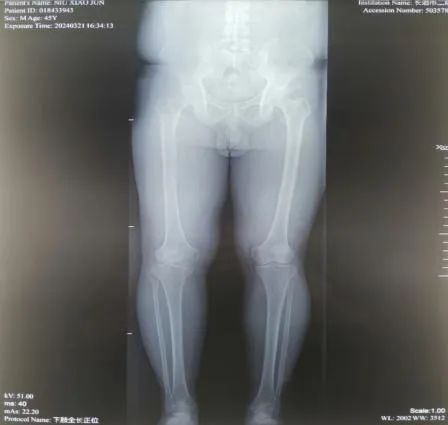

45岁的患者牛某,因5年前外伤致右胫骨平台骨折,未行手术治疗,伤后半年开始负重行走,致使右膝关节不稳定,且逐年加重。患者因右膝关节不稳定,不敢快速行走及下台阶,且摔倒数次,产生了恐惧心理。辗转多家医院后,均疗效不明显。 听闻“京长合作”首都医科大学附属北京积水潭医院每月定期派专家来长治二院骨科坐诊、查房、手术的医讯,主动要求北京积水潭专家手术治疗,近日来我院就诊要求住院手术治疗。 门诊经查体及阅读各项检查后以“右胫骨平台骨折畸形愈合”便收住院。 入院诊断: 1.右胫骨平台骨折畸形愈合 2.高血压病 住院期间,北京积水潭医院骨科吴宏华副主任医师结合查体及辅助检查,考虑患者畸形为关节外畸形,下肢力线向前内侧偏移,建议行胫骨内侧高位双平面截骨纠正对位及力线。考虑开放行双平面截骨,创伤较大,建议3D打印HTO截骨导板,在导报引导下行微创双平面截骨。在全身麻醉下在截骨导板引导下行截骨矫形术。 术后3天患者牛某持助行器下地行走,右膝关节不稳定感觉消失,恐惧心理消失,心情舒畅,对手术效果非常满意。 此次手术是在北京积水潭吴宏华副主任医师指导下,长治二院首次将HTO截骨技术应用于创伤骨科,是“京长合作”带给长治二院骨科发展的新动力,更为我市骨病患者带来的福音。 科室推荐 创伤骨科二病区隶属于长治二院骨科创伤专业,成立于 1978年建院之初,至今已历时 40 余年。创伤二病区现有开放床位 35 张,共有医师 10名(含返聘医师),护士 9 名。其中主任医师 1名,副主任医师 1 名、主治医师 6名、住院医师 2 名。 病区主任:李黎明,主任医师、长治市工伤医疗鉴定专家、北医三院进修学员,擅长复杂骨折的手术修复,尤其在骨盆骨折、关节周围骨折的手术治疗方面技术精湛。 创伤二病区诊疗疾病范围:肩胛骨骨折、肩(胸)锁关节脱位、锁骨骨折、肱骨近段骨折、肱骨干骨折、肱骨髁骨折、尺骨鹰嘴(冠突)骨折、尺桡骨骨折、桡骨远端骨折、各类型骨盆骨折、髋臼骨折、股骨头骨折、股骨颈骨折、股骨粗隆间骨折、股骨干骨折、股骨髁骨折、髌骨骨折、胫骨平台骨折、胫腓骨骨折、各类型踝关节骨折(韧带损伤)、各类型开放(闭合)性软组织损伤、陈旧性骨折不愈合、骨感染(骨髓炎)、内固定周围骨折、骨折非手术治疗、骨折康复指导等。 咨询热线 0355—3126025 主任医师 创伤骨科二病区主任 擅长复杂四肢骨折、骨盆骨折,脊柱骨折、颈椎病、腰椎管狭窄等的诊治。在肢体复杂损伤、脊柱退变疾病方面有较多深入研究。多次在北京、太原等省内外三甲医院进修学习,具有丰富的理论知识。 【学术任职】 长治医学院副教授、长治市骨科专业委员会委员、长治市足踝外科委员会委员、长治市医疗专家库成员,长治市工伤、司法鉴定专家组成员。在国家级省级专业杂志发表论文学术论文10余篇,在专业学术领域积累了丰富的临床经验。 医生推荐 徐彦芳 副主任医师 骨科学硕士 北京大学国内访问学者 【专业特长】 【学术任职】 咨询热线 李黎明主任 13097569000 徐彦芳医生 15635598825 供 稿丨徐彦芳 编 辑丨卞 晨 审 核丨雷 赫